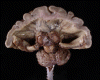

Frontal view:

On the frontal view, the two cerebral hemispheres appear to be fused in the

midline although there is a falx like structure at the midline. In contrast,

the cerebellum and the medulla seems to have split well into the right and

left half.